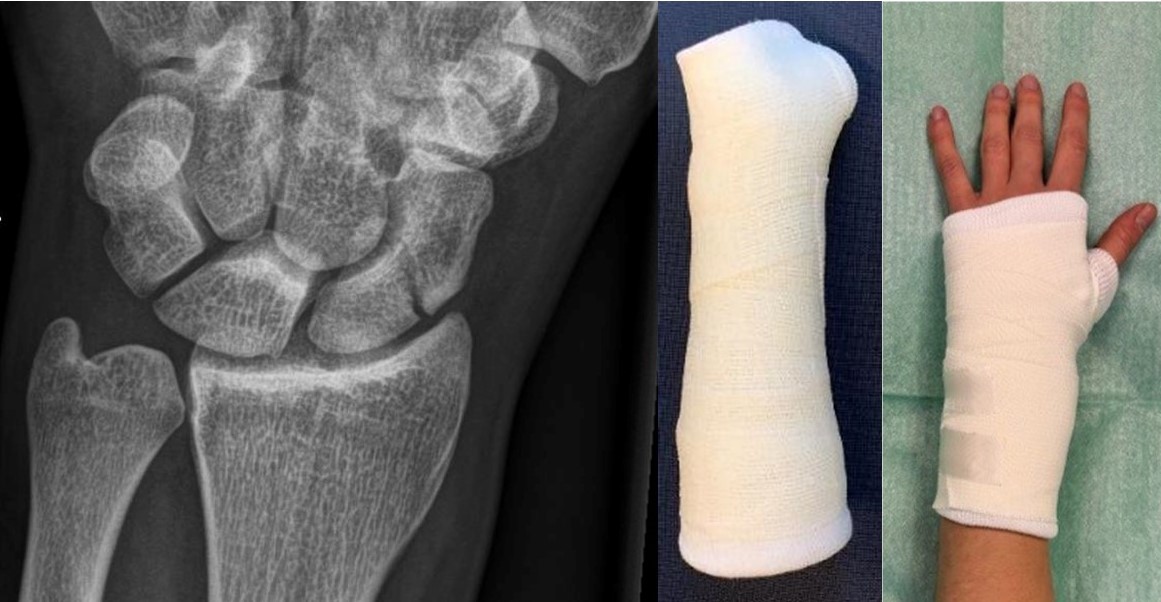

During my PhD, I focused on the underlying neural and neuromuscular mechanisms of postural control in ageing. During my current post-doc position, the goal is to implement a new treatment for clinically suspected scaphoid fractures, whereby the primary treatment should be bandaging instead of casting.